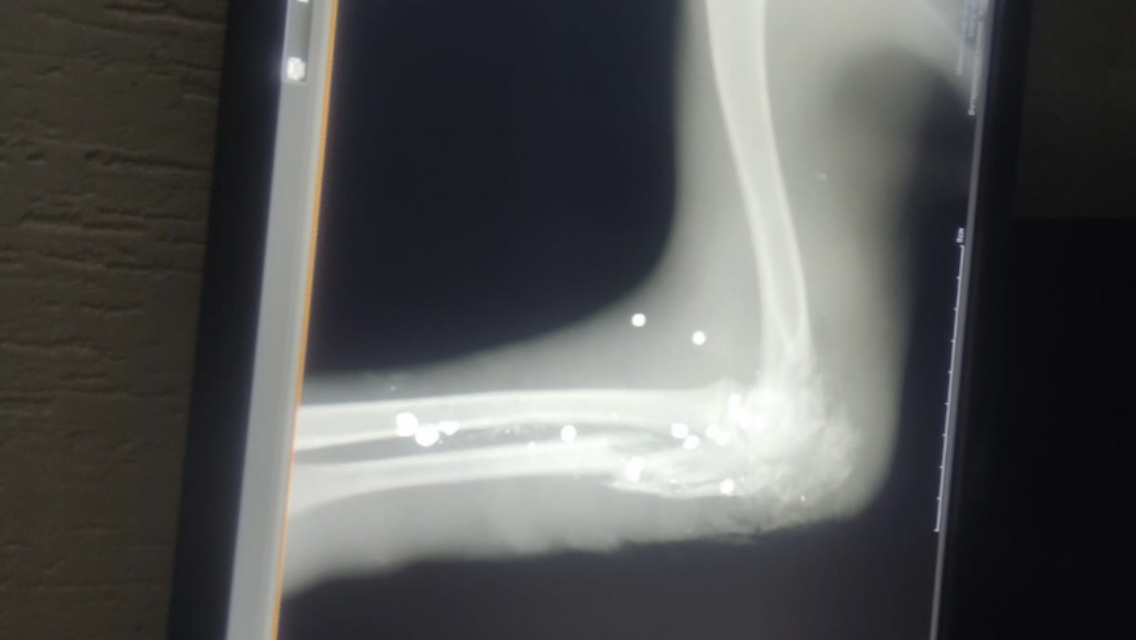

К нам попал пёсик, ещё щенок, не мог становится на лапу.

Рентген показал пу_ли в лапке. Точно не могу сказать, но я насчитала 8

Кроме того, что задета кость, пере_биты все нервные окончания. Полное отсутствие ГБЧ (глубокая бо_левая чувствительность). Пришлось лапу амп_утир_овать.